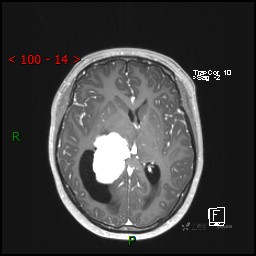

视物模糊发现颅内占位,“豆蔻年华”却承受开颅之痛,所幸一切顺利---结果公布~

患者年龄:14岁

简要病史:患者于1月前无明显诱因出现视物模糊,无明显头痛头晕,无恶心呕吐,无昏迷,无肢体偏瘫等症状,就诊于当地医院头部CT考虑:右侧丘脑、脑室占位。予以对症处置后家属为求进一步诊治来我科,以“颅内占位”收入院。 起病以来,精神、饮食、睡眠欠佳,大小便正常,体力下降,体重无明显变化。

临床诊断:脑室占位

MRI平扫